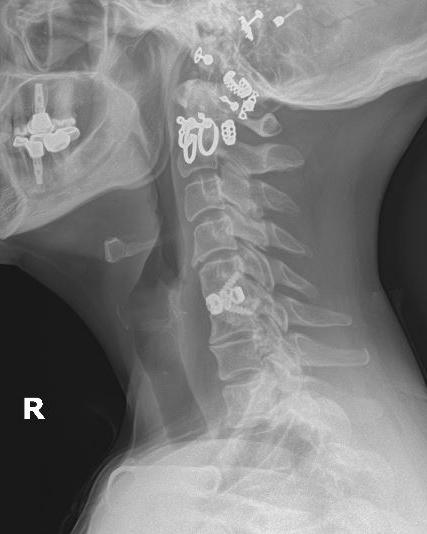

Achieving sagittal alignment involves balancing the cranium, spine, and pelvis through key measurements: pelvic incidence (PI), pelvic tilt (PT), lumbar lordosis (LL), thoracic kyphosis (TK), cervical lordosis (CL) and C7 plumb line/sagittal vertical axis (SVA).6,7 Each person’s individual measurements vary

15 isass.org Spring 2024 Vertebral Columns

Annika Heuer, MD1,2 Eric Kim, BS1 Myles Allen, MBChB1 Tomoyuki Asada, MD13 Sheeraz A. Qureshi, MD, MBA1

slightly, with normal ranges typically falling within the following ranges: PI = 55° ± 10°, PT <20°, LL = 60°, TK = 20°–50°, CL = 20°–40°, and SVA with a C7 plumb line distance = ± 4–5 cm.8-10 However, with advancing age, individuals tend to adopt a more forward-leaning posture and seem to tolerate slightly more positive sagittal alignment values. Factors contributing to sagittal imbalance include any condition that shifts the body’s center of gravity forward. To counterbalance forward bending, the cervical spine can adjust with an exaggerated lordotic curve to achieve a stance that appears more neutral.10,11 Furthermore, compensation can include increased pelvic tilt and knee flexion, which leads to a physically straining, fatiguing position to maintain. 8,12

The significance of both regional and global spinal alignment is critical, especially when considering the impact of degenerative changes on overall posture and balance. To accurately assess global sagittal balance—including the regional cervical spine—it is often necessary to conduct full-length standing radiographic examinations, though these are not always considered essential for all patients with an isolated cervical pathology in daily clinical practice. However, there is a growing need for further research to understand the interactive effects of these factors better and to establish the value of comprehensive radiographic evaluation in the planning stages of spinal surgery. 9,19